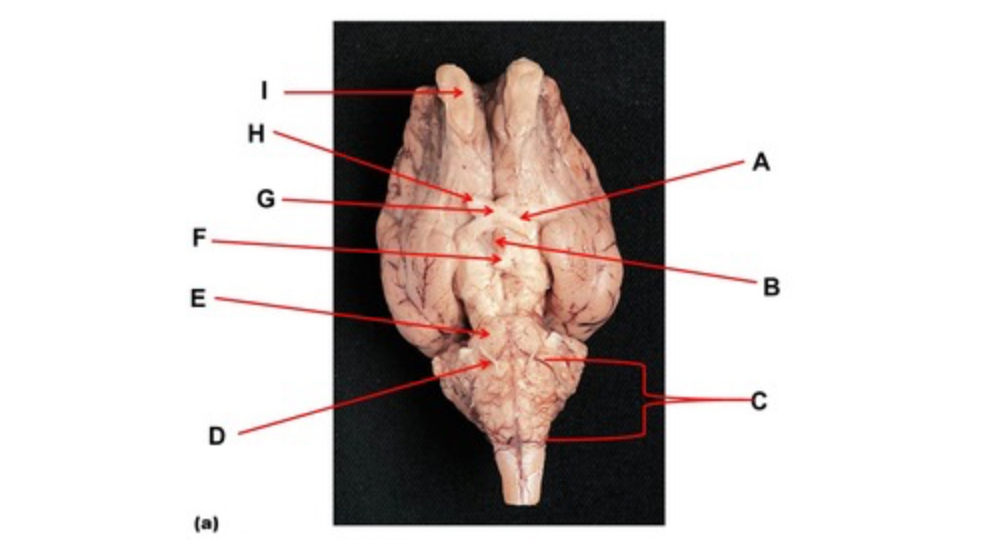

Name the region within bracket D.

medulla

Name the region within bracket D

medulla

Name the deep groove at the tip of arrow G.

anterior median fissure